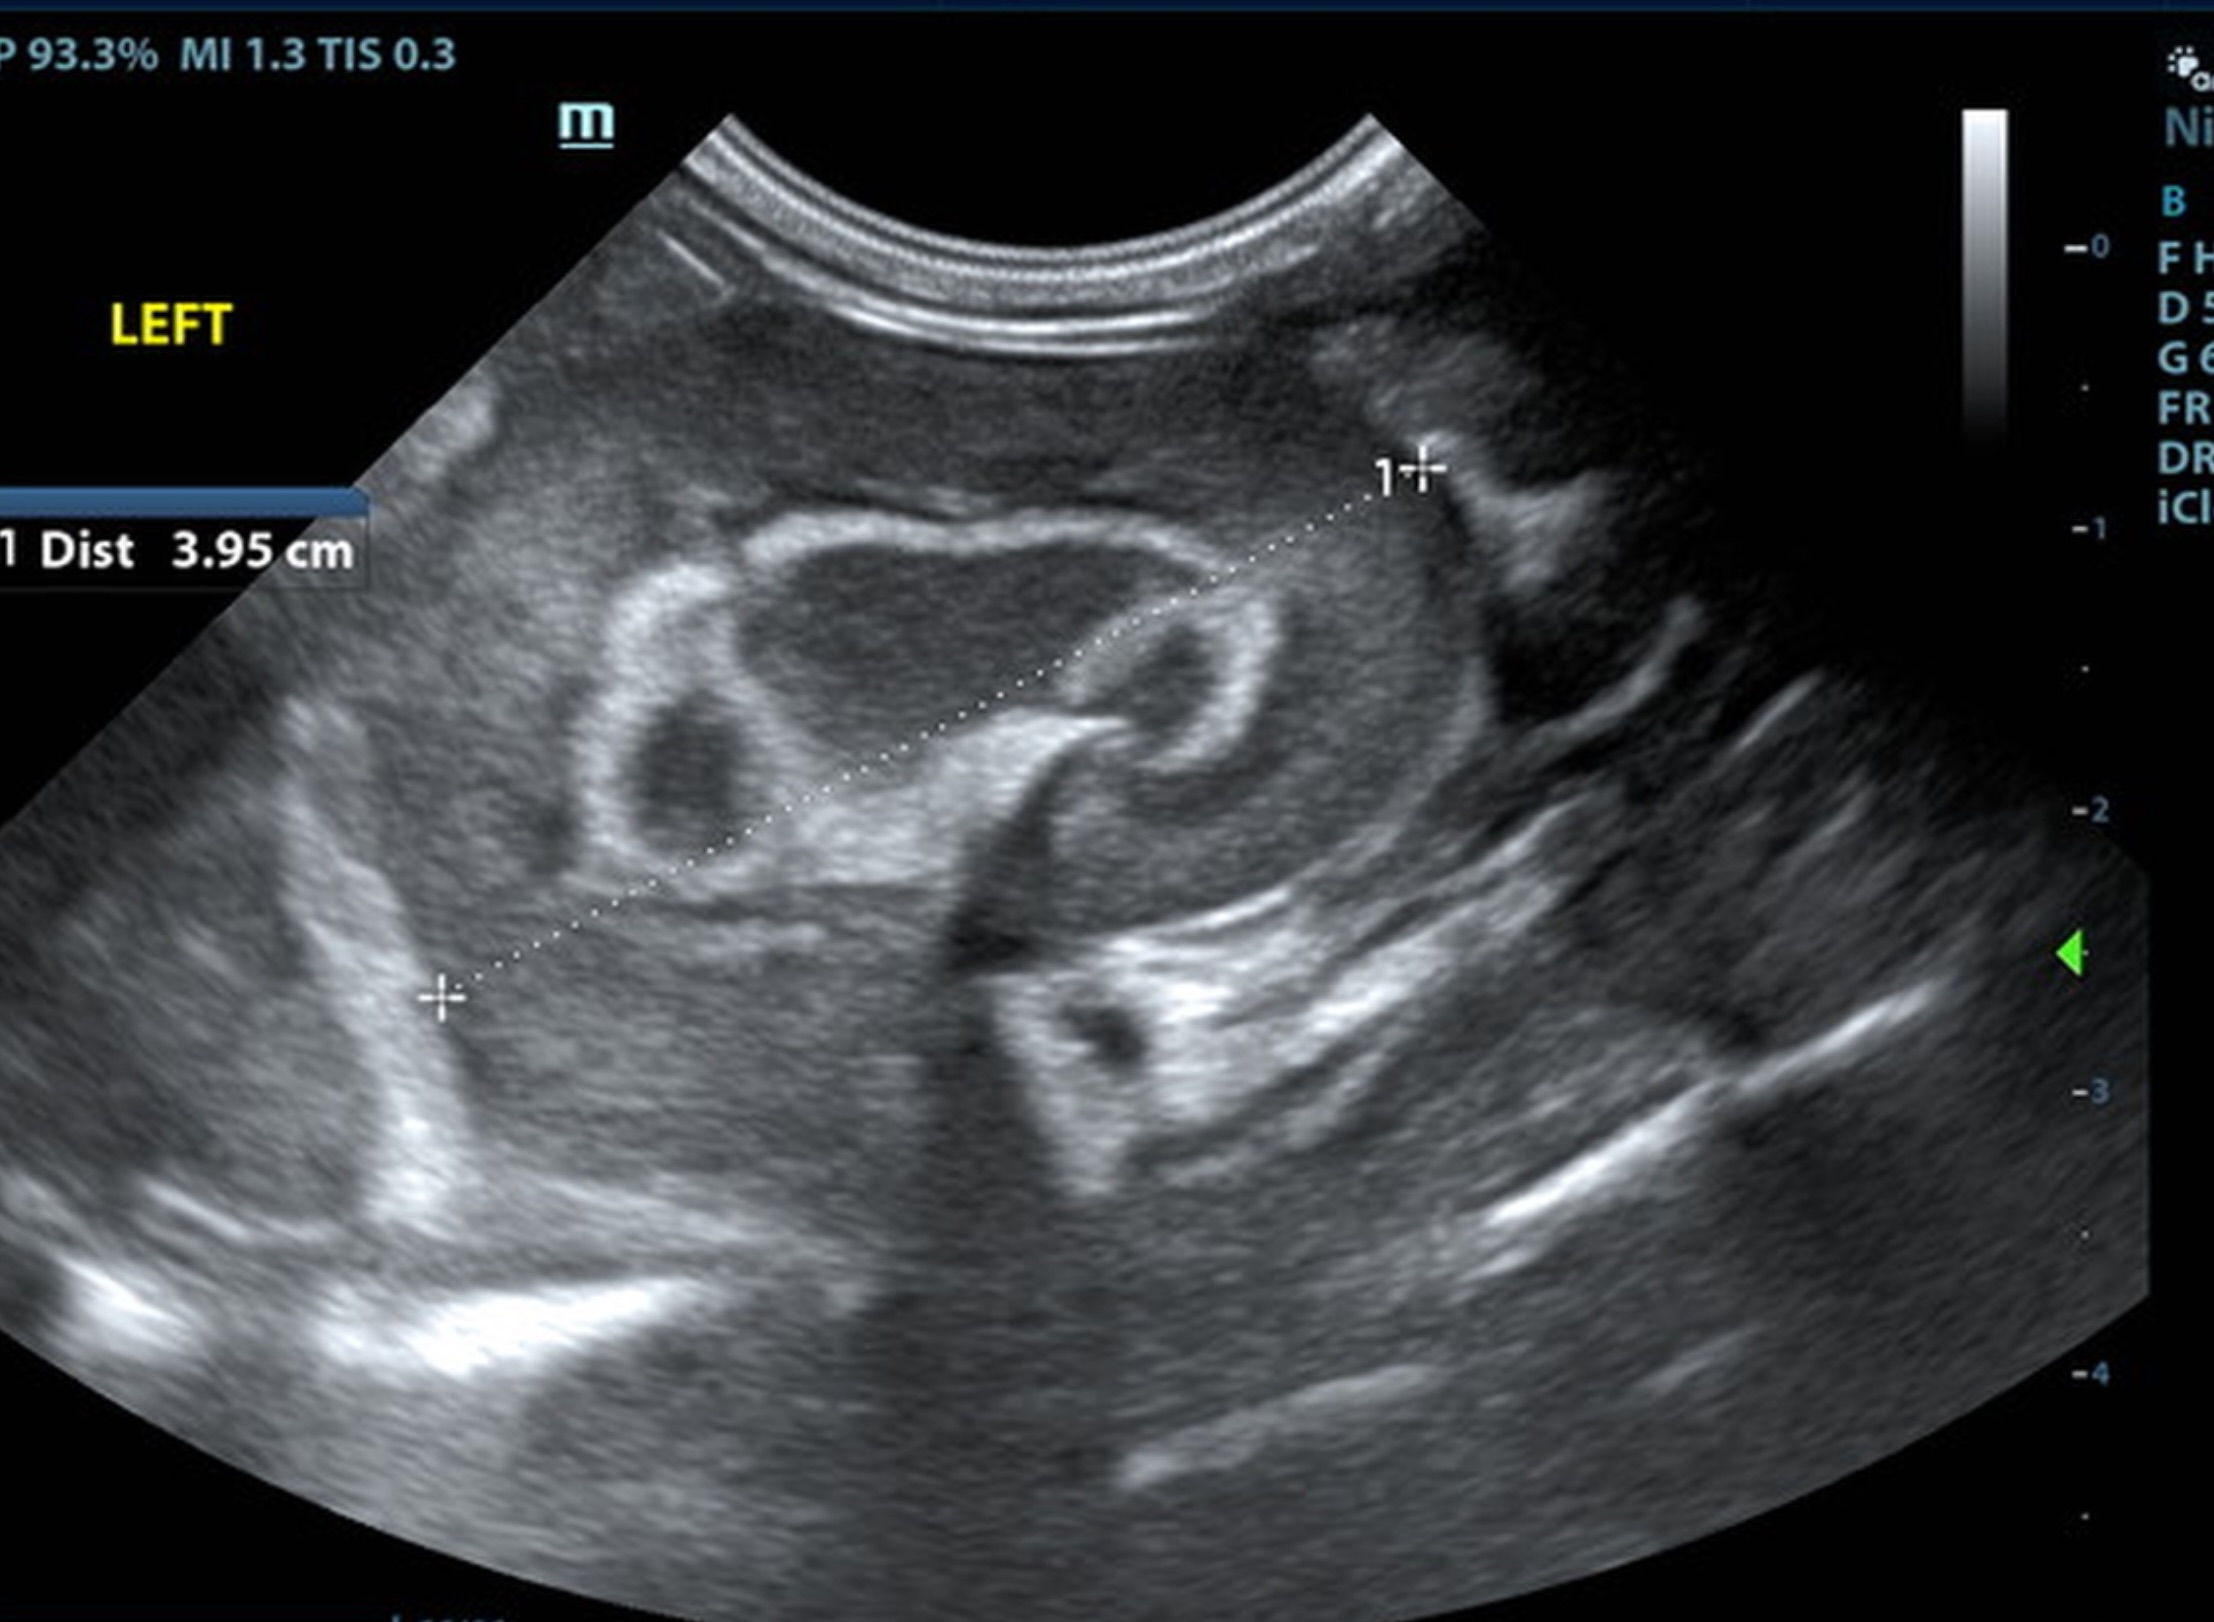

The kidneys were swollen with hyperechoic, mineralized medullary rim sign. The right kidney measured 4.0 cm. The left kidney measured 3.95 cm.